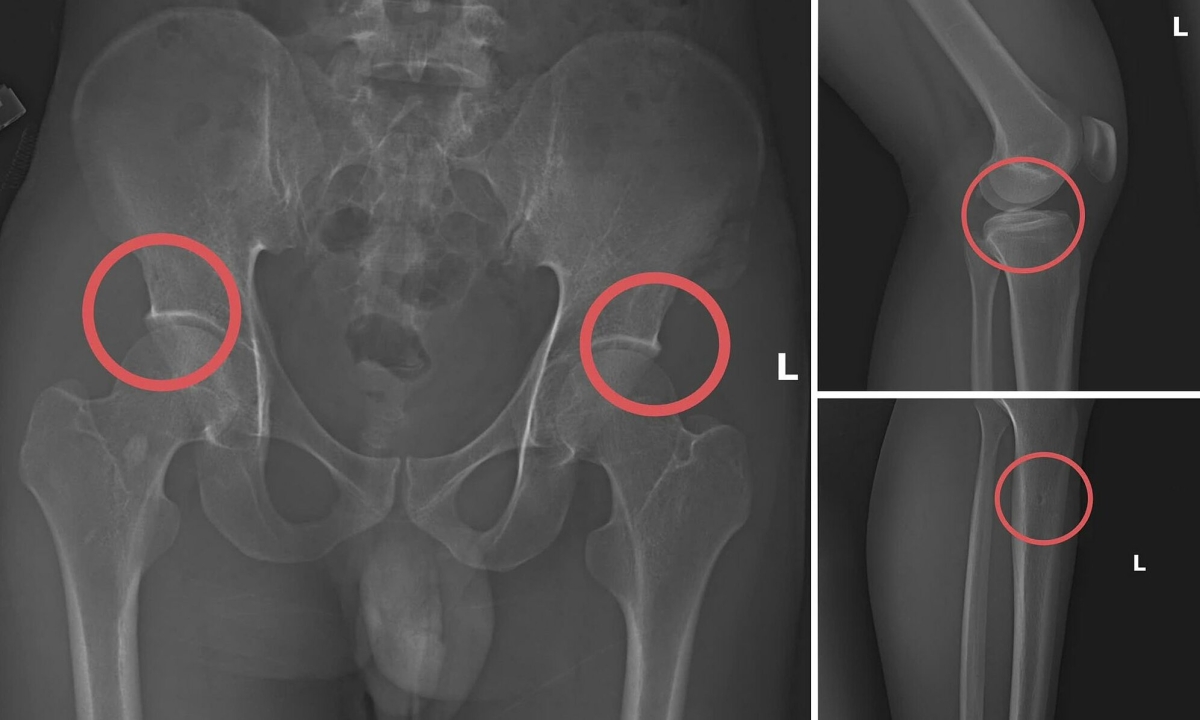

Châu trực tiếp thực hiện hành vi tiêm thuốc mê rồi dùng kim tiêm, búa đinh để tác động vào xương người mua bảo hiểm. Sau khi can thiệp đã tạo nên các vết nứt, vỡ xương giống hệt bị tai nạn thật. Tạo thương tích xong, anh ta tiếp tục hướng dẫn đồng phạm dựng hiện trường giả như điện giật ngã, trượt chân ngã suối nhằm hợp thức hóa bệnh án và hoàn thiện hồ sơ yêu cầu chi trả.

Công an Phú Thọ đánh giá, đường dây này hoạt động có tổ chức, tinh vi nhằm qua mặt cảnh sát. Thủ đoạn "tàn nhẫn, vô nhân tính, coi thường sức khỏe, tính mạng của người tham gia". Chúng đã lên kế hoạch, tính toán kỹ để gây thương tích đúng vị trí có mức chi trả cao, khiến các công ty bảo hiểm khó phát hiện dấu hiệu gian dối.